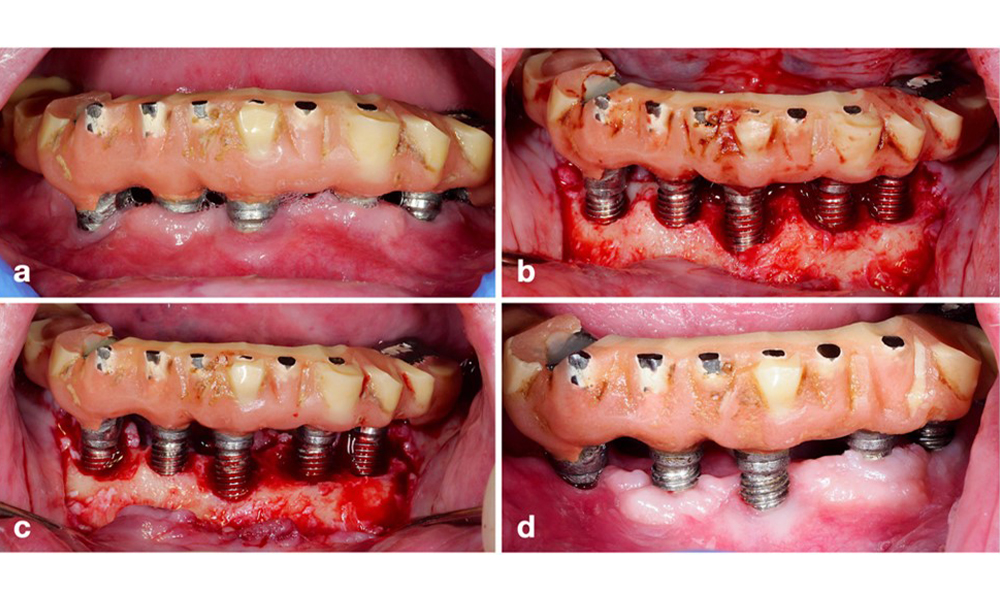

La péri-implantite est identifiée par (1) des signes d'inflammation similaires à la mucosite, (2) des preuves radiographiques de perte osseuse après la cicatrisation initiale et (3) une augmentation de la profondeur de sondage par rapport aux mesures prises peu après la mise en place de la reconstruction prothétique (figure 2). En l'absence de radiographies antérieures, un niveau osseux radiographique de ≥ 3 mm, accompagné d'un saignement au sondage et d'une profondeur de sondage ≥ 6 mm, indique une péri-implantite.

Restauration de l'arcade complète avec péri-implantite à des degrés divers sur certains implants. L'implant en position 21 est sévèrement atteint avec des profondeurs de sondage allant jusqu'à 9 mm (a), un saignement au sondage, une suppuration du sillon péri-implantaire et une fistule vestibulaire (b-c) ; la radiographie montre une perte osseuse d'environ 50 % pour l'implant atteint de péri-implantite en position 21, tandis que l'implant en position 23 présente une perte osseuse limitée, correspondant approximativement à ce que l'on peut attendre après la cicatrisation initiale pour ce type d'implants (d).

Figure 2. Restauration de l'arcade complète avec péri-implantite à des degrés divers sur certains implants. L'implant en position 21 est sévèrement atteint avec des profondeurs de sondage allant jusqu'à 9 mm (a), un saignement au sondage, une suppuration du sillon péri-implantaire et une fistule vestibulaire (b-c) ; la radiographie montre une perte osseuse d'environ 50 % pour l'implant atteint de péri-implantite en position 21, tandis que l'implant en position 23 présente une perte osseuse limitée, correspondant approximativement à ce que l'on peut attendre après la cicatrisation initiale pour ce type d'implants (d).

La perte osseuse attendue après la cicatrisation initiale, attribuée au remodelage de l'os marginal, varie en fonction de facteurs tels que le système ou le type d'implant. Par exemple, une perte osseuse de 1 à 2 mm est généralement considérée comme "normale" pour les implants au niveau de l'os avec une connexion externe (figure 2d, implant en position 23).